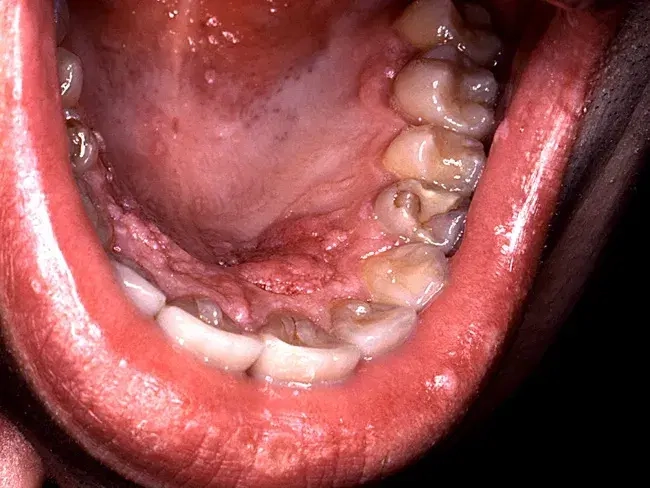

A clinical depiction of genital warts